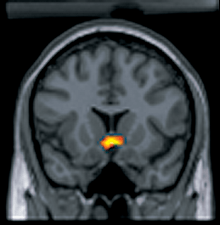

Mapping and lesion studies on BSR were designed to determine the location of reward-relevant neurons as well as determine the signal pathways that are directly affected by brain stimulation. The site of intracranial self-stimulation leads to substantially different behavioral characteristics. Sites along the length of the medial forebrain bundle (MFB) through the lateral and posterior hypothalamus, the ventral tegmental area (VTA), and into the pons are associated with the strongest reward effects of stimulation.[1]

The mesolimbic pathway contains the VTA, nucleus accumbens, amygdalae, and the medial prefrontal cortex. The nucleus accumbens is a part of the striatum that integrates information from cortical and limbic brain structures to mediate behaviors the reinforce reward .[13] The nucleus accumbens is a major target for the dopaminergic projections from the brainstem that are associated with BSR. The VTA is a group of neurons located close to the midline on the floor of the midbrain, and VTA is the origin of dopaminergic cell bodies that comprise the mesocorticolimbic dopamine system.[3]

The mesolimbic pathway is activated trans-synaptically by normal rewards (food, water, copulation) but it can also be activated directly by the induced rewards of intravenous drugs or electrical or chemical brain stimulation.[9] The mesolimbic pathway is one of the dopaminergic pathways in the brain that modulates behavioral responses to rewarding stimuli. It originates in the VTA and connects to the limbic system via the nucleus accumbens, the amygdala, and the medial prefrontal cortex. A number of drugs are rewarding when they are injected into the nucleus accumbens and act as mesolimbic dopamine terminals,[14] and the axons of the mesolimbic dopamine system have high thresholds for stimulation .[9]